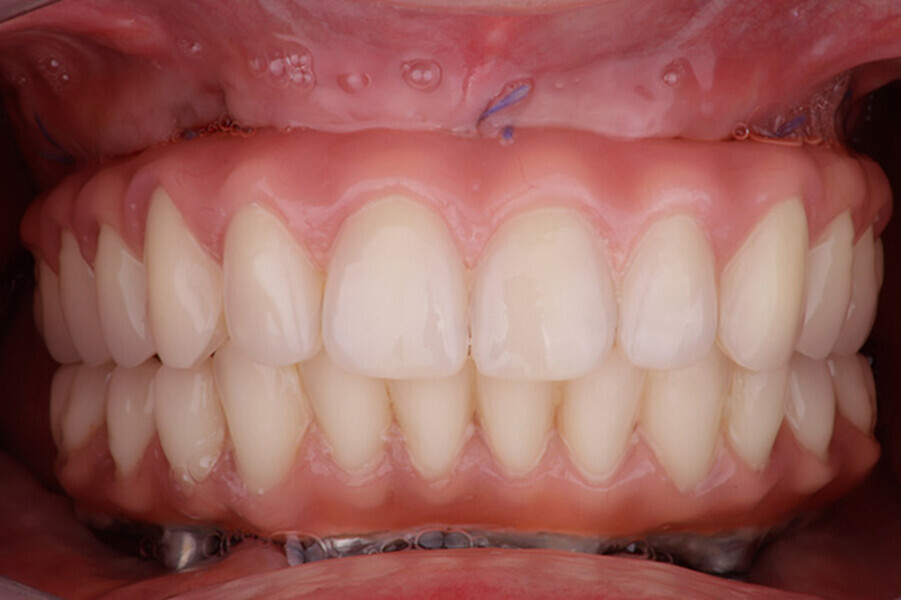

Fig. 4 Prótesis Híbrida inmediata y radiografía control con 6 años post-operatorio

Fig. 5. Prótesis Híbrida inmediata y radiografía control con 6 años post-operatorio